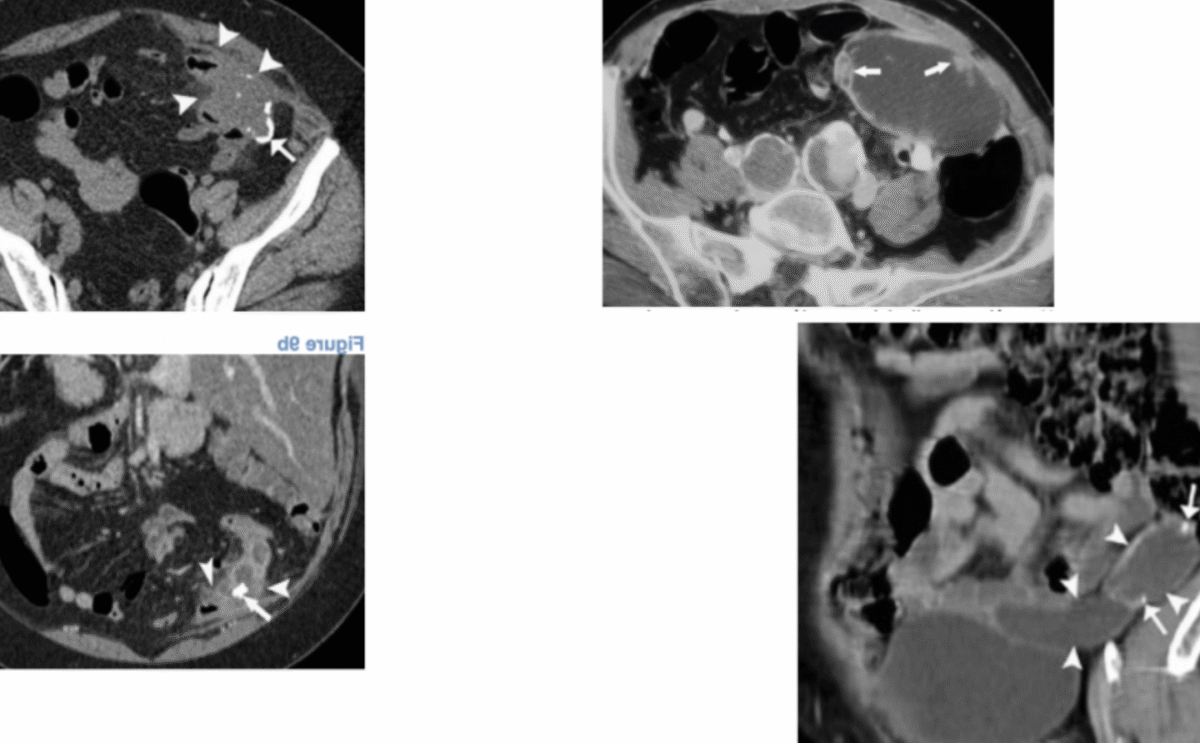

Le scanner abdomino-pelvien est une technique d’imagerie médicale qui utilise les rayons X associés à l’informatique pour obtenir des images en coupes transversales ou axiales de l’abdomen et du pelvis. Il permet d’examiner les organes internes comme le foie, la vésicule biliaire, le pancréas, les reins, la vessie et les organes génitaux. Cette procédure est fréquemment utilisée pour détecter ou suivre l’évolution de pathologies telles que les masses, les kystes, les calculs rénaux ou les anomalies de l’appareil digestif.